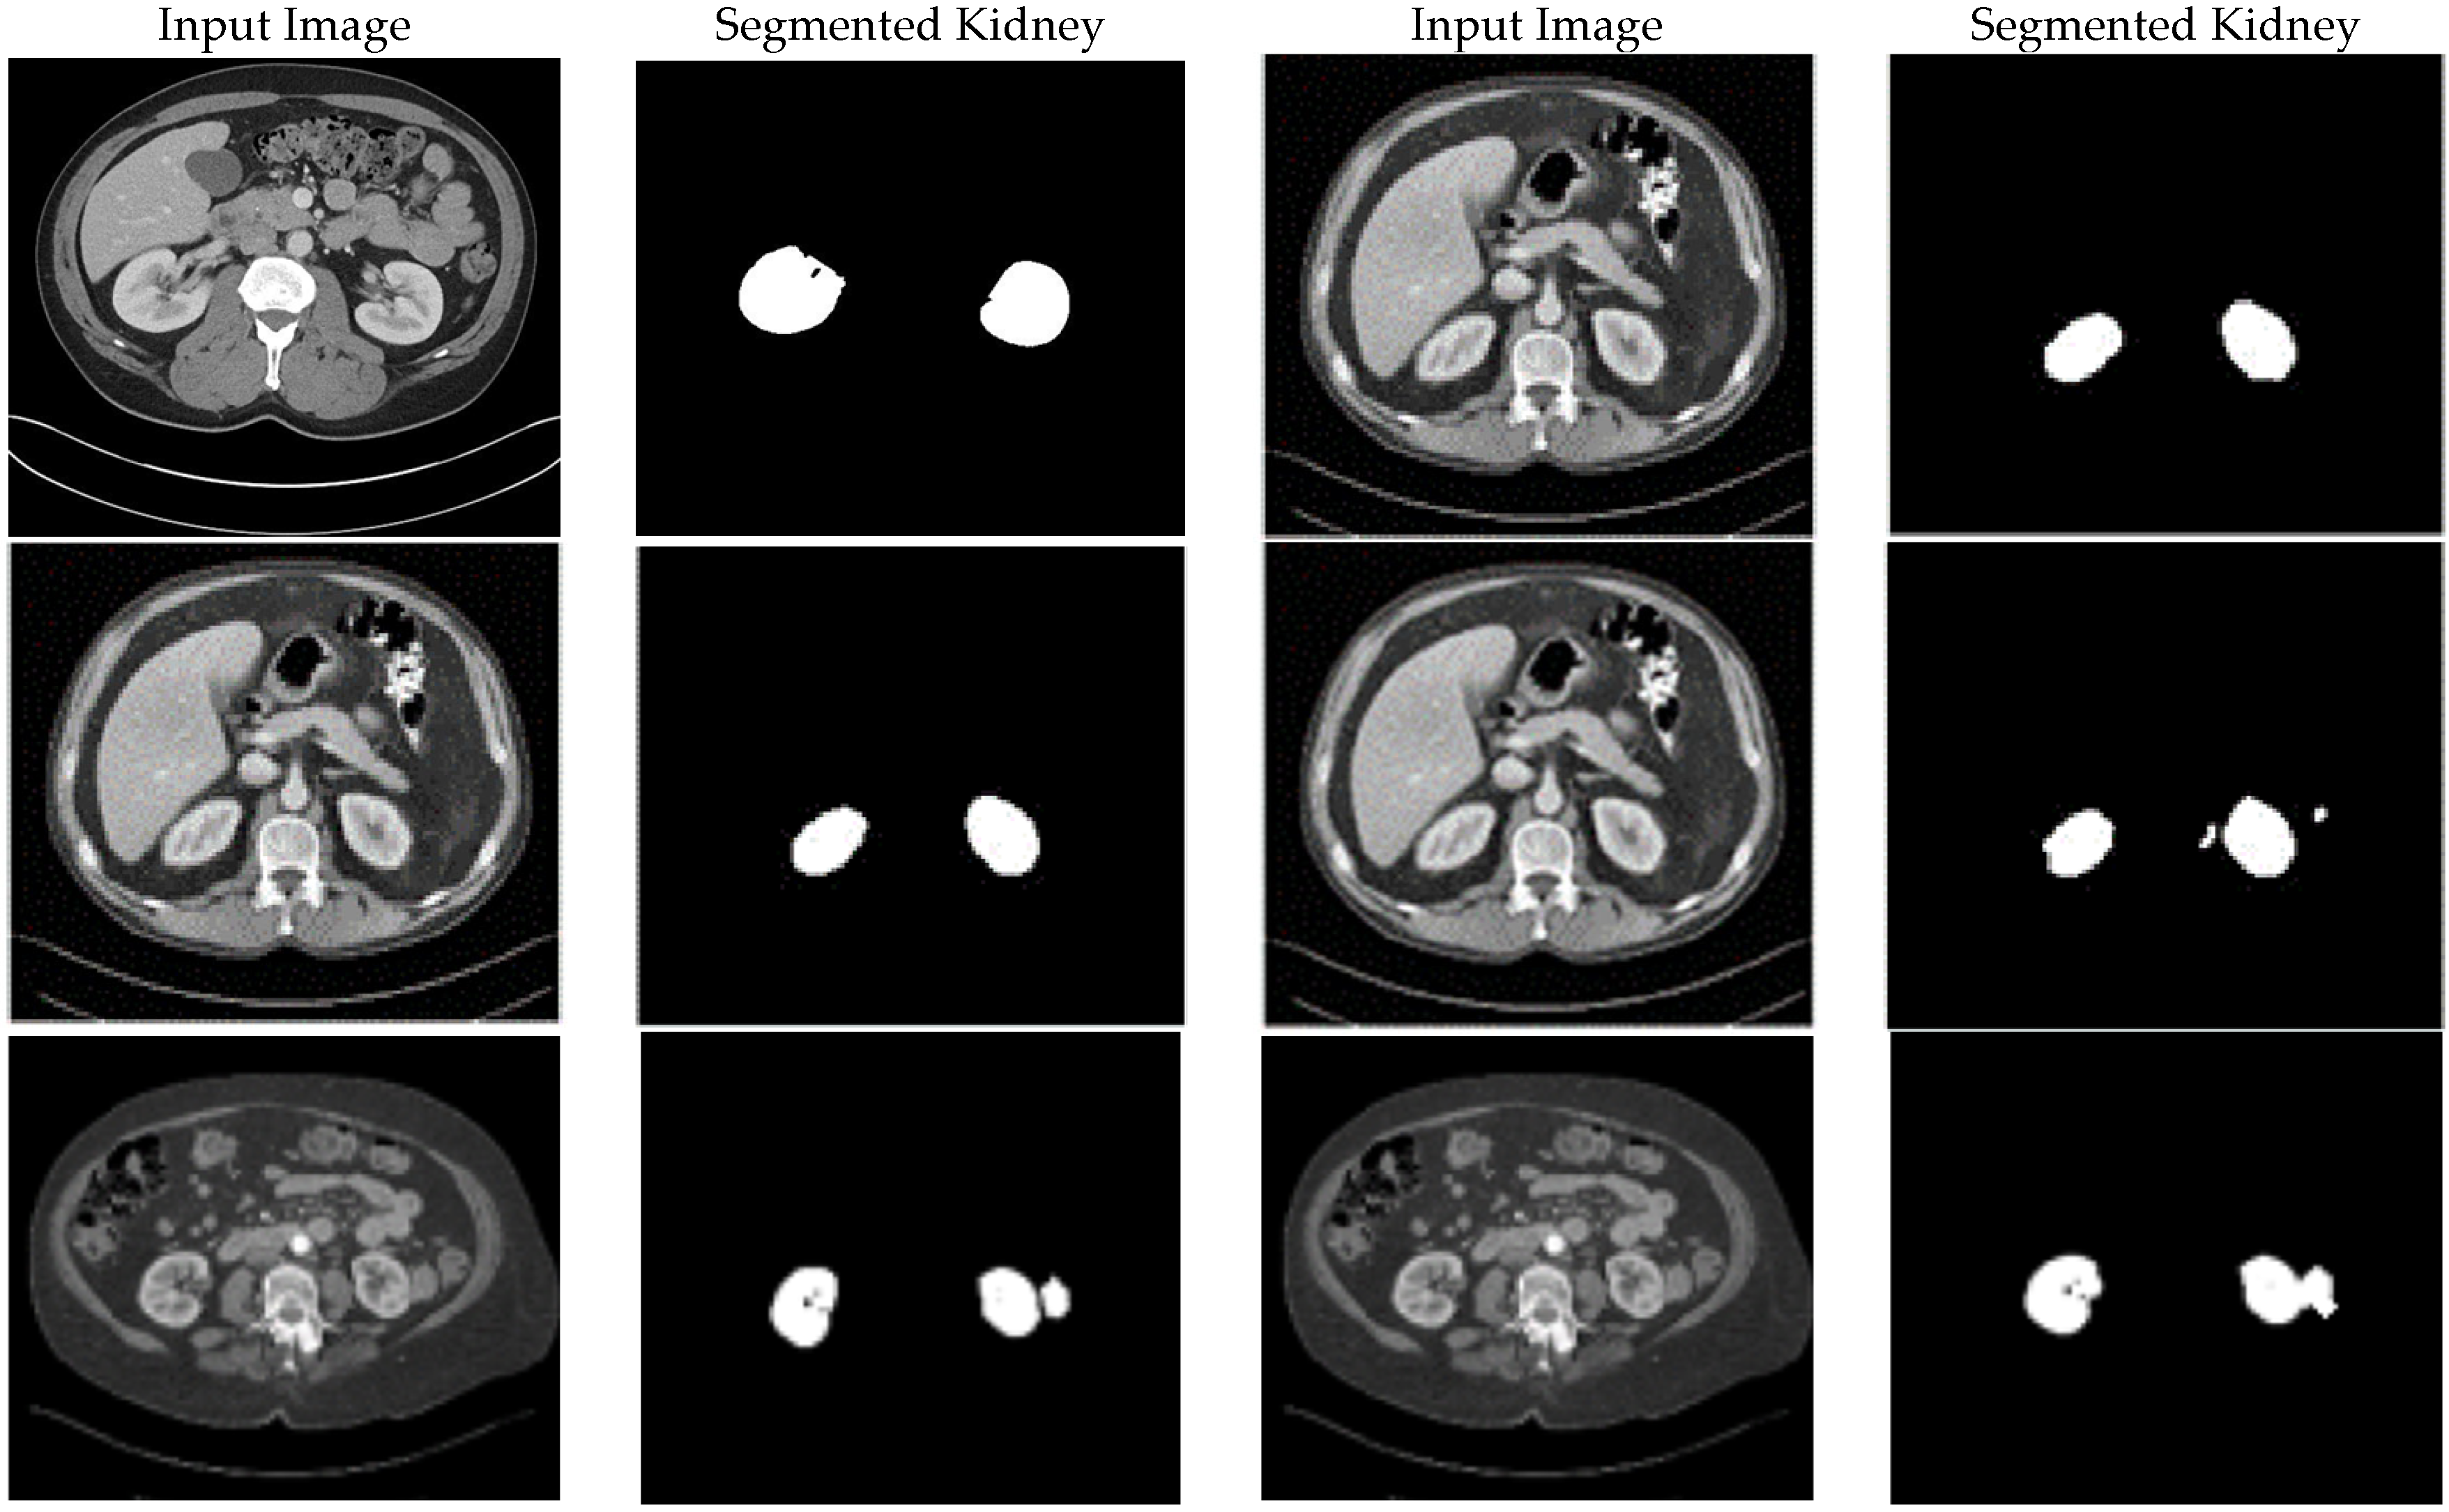

4.3.3. Segmentation Performance (KiTS19)

The original dataset (300 cases) and the improved datasets (900 cases total: 300 × 3) were used to train the two CNN models for the KiTS19 dataset. The improved datasets were used to train CCNN, and the fuzzy entropy-based dataset produced the best-performing model (BRISQUE: 23.1). Dice coefficient, accuracy, precision, sensitivity, and recall were used to assess performance. The BRISQUE scores and segmentation accuracy of the three models are contrasted in Table 4.

Both the original and CLAHE-filtered datasets fared worse than the suggested enhancement pipeline. The BRISQUE score of the original KiTS19 dataset was 28.8, but CLAHE raised it to 26.4. Our approach produced better image quality with a lower BRISQUE score of 21.7. The significant influence of our enhancement strategy on segmentation performance was demonstrated by the CCNN model trained on our enhanced dataset, which achieved an accuracy of 0.983, a 2.4% improvement over the CLAHE-filtered dataset (0.959), and a 6.2% improvement over the original dataset (0.921). Figure 5 includes a sample visualization of the segmentation results.

The suggested improved CCNN model obtained the highest scores on all metrics: a Dice coefficient of 99.60%, precision of 98.70%, sensitivity of 99.30%, and recall of 98.60%. Table 7 and Figure 6 provide a thorough comparison of segmentation performance for kidney tumor segmentation, mainly on the KiTS19 dataset. With a 99.60% alignment rate, the suggested model outperforms the best option, LinkNetB7, by 2.40% (97.20%). The Dice coefficient, a crucial parameter for segmentation tasks, quantifies the overlap between predicted and ground truth segmentations. In terms of precision (98.70%), the model outperforms LinkNetB7 (97.30%) by 1.40%, indicating that 98.7% of projected tumor pixels are accurate. The suggested model’s improved ability to identify real tumor regions while reducing missed detections is demonstrated by its maximum sensitivity (99.30%) and recall (98.60%), which gauge the percentage of genuine tumor pixels properly recognized. LinkNetB7 trails at 97.00% for both.

There are clear patterns among the models in Table 7. Modern deep-learning architectures are effective at kidney tumor segmentation on KiTS19, as evidenced by the Dice coefficients above 96% achieved by the majority of algorithms, including EfficientNetB5 (96.90%), UNet2d (96.33%), UNet3d (96.90%), and LinkNetB7 (97.20%). However, older or less specialized models, such as Ensemble CNN (85.00%) on KiTS19 and UNet3d (87.50%) on DCE-MRI by Haghighi et al., trail significantly. This is probably because the datasets are different (DCE-MRI vs. KiTS19) or because simpler ensemble techniques are unable to capture small tumor borders. Precision varies greatly; although models such as Ensemble CNN (91.00%) and Haghighi et al. (92.70%) exhibit greater rates of false positives, EfficientNetB5 (97.47%) and LinkNetB7 (97.30%) perform well. The suggested model’s 99.30% sensitivity and 98.60% recall set a new standard. Sensitivity and recall are less frequently reported, but when they are, they vary from 95.32% (Da Cruz et al.) to 97.00% (LinkNetB7). When compared to models trained on unenhanced or differently treated data, the suggested CCNN’s consistent superiority across all criteria indicates that the enhancement pipeline greatly improves segmentation performance.